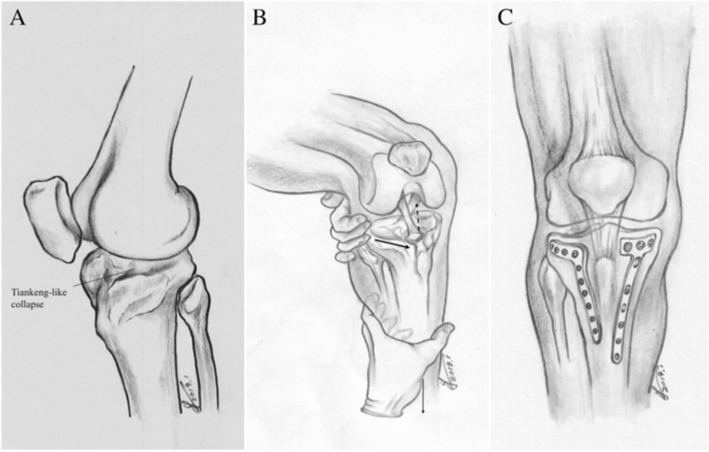

Fig. 2.

Schematic diagram describing fracture characteristics, reduction technique and fixation method. a Tiankeng-like collapse. b reduction technique. pulling the proximal metaphysis of the tibia forward(thick arrow) and pulling the distal end of the tibia distally(thin arrow), Tiankeng-like collapsed fragment would be reduced by ligamentotaxis(dotted arrow). c Double plates to fix hyperextension bicondylar tibial plateau fractures

As most of the hyperextension-type bicondylar tibial plateau fractures are characterized by central depression of the anterior part of the medial plateau, lateral plateau, and the median eminence as a whole, while the cortices of the plateau may lie in situ (similar to the geographic fracture “Tiankeng”), we termed this central depression as “Tiankeng-like collapse.” It is inconvenient to observe the Tiankeng-like collapse from the side, but easy to expose the whole Tiankeng-like collapse from the window behind the patellar ligament. Thus, the patellar ligament can be retracted medially or laterally to reveal the Tiankeng-like collapse through the modified anterior midline incision. For severely comminuted cases or old fractures, tibial tuberosity osteotomy can be performed to increase the anterior exposure of the modified anterior midline incision.

A longitudinal incision was performed parallel to the anterior midline of the knee, starting from the upper edge of the patellar, passing the lateral edge of the tibial tuberosity and approximately 1 cm lateral to the anterior tibial spine, and then extending approximately 7 cm distally. The full-thickness flap was protected, directly exposed to the deep fascia, stripped to both sides, and then exposed to the anterior edge of the fibular head laterally and the anterior edge of the superficial medial collateral ligament (MCL) medially. The flap was carefully retracted, and the lateral patellar retinaculum was incised, with a tibial tuberosity osteotomy performed occasionally to increase the anterior exposure, to obtain a 50–70-mm-long, 20-mm-wide proximal-end, 15-mm-wide distal end, and 10-mm-thick bone fragment in relation to its insertion in the tibial tubercle. The bone flap was then retracted proximally. Next, the anterior tibial muscle fascia was cut longitudinally, and the tibial is anterior muscle retracted laterally. A medial subperiosteal dissection was then used to reveal the medial fracture line. If the articular surface of the tibial plateau had a gap or step-off, the medial and lateral menisci were elevated to inspect the underlying joint surface. For restoration of sagittal plane alignment, disimpaction and elevation of the anterior metaphysis was performed by pulling the proximal metaphysis of the tibia forward and pulling the distal end of the tibia distally with the knee in the flexion position. The periosteal elevator was often used to reduce the collapsed fragments.

After reduction was accomplished, the Kirschner wire was used for temporary fixation. Allograft bone was used for most cases. The C-arm was adopted to confirm the reduction, and a T-shaped locking plate was placed in front of the MCL medially, and an L-shaped locking plate was placed on the lateral side, to fix the fracture. Once again, the C-arm was used to confirm that the articular surface was smooth, the pTSA was recovered, and the position of internal fixation was satisfactory. The wound was flushed with saline, the drainage tube was indwelled, and the deep fascia was sutured intermittently. The parapatellar retinaculum and the anterior tibialis fascia were repaired, and the superficial fascia and skin was intermittently sutured in favor of drainage.